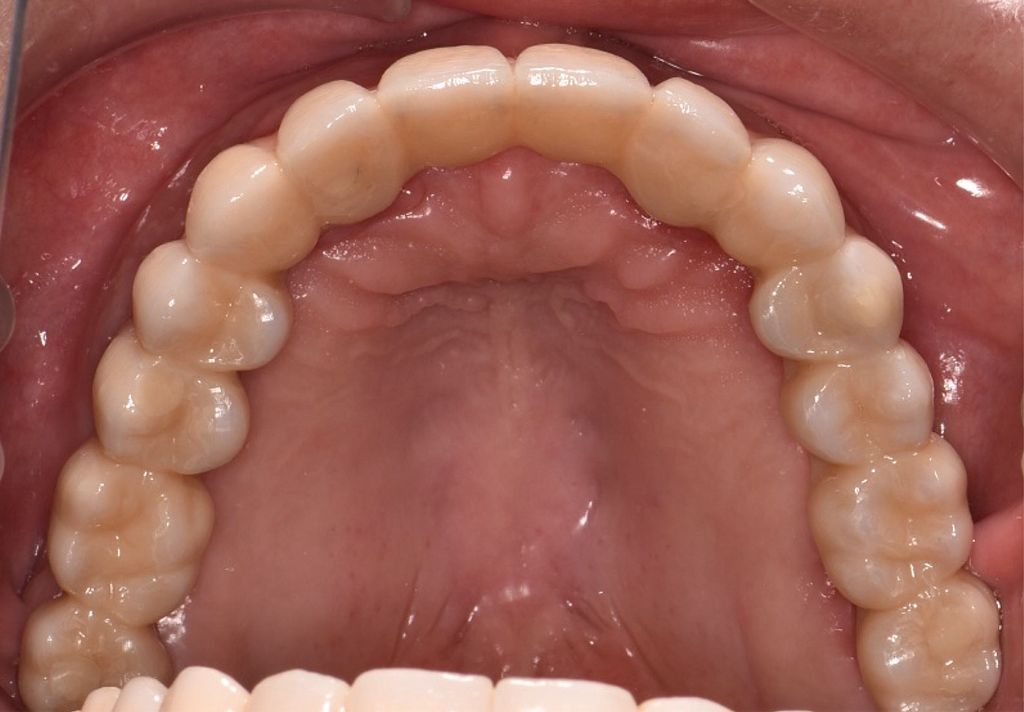

After